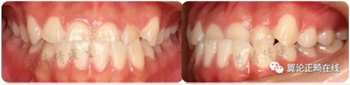

一個(gè)恒牙列早期的骨性3類小女生,沒有顯著家族遺傳史。

磨牙尖牙均為近中關(guān)系,前牙反覆頜較深,下切牙舌傾代償(IMPA=88.8度)。下頜可以功能性后退至切對(duì)切。

從軟組織面型上看,患者面中份發(fā)育尚可,面下1/3發(fā)育過度。下唇外翻明顯。

治療后咬合狀態(tài)、側(cè)貌、以及微笑弧等都得到很大改善。